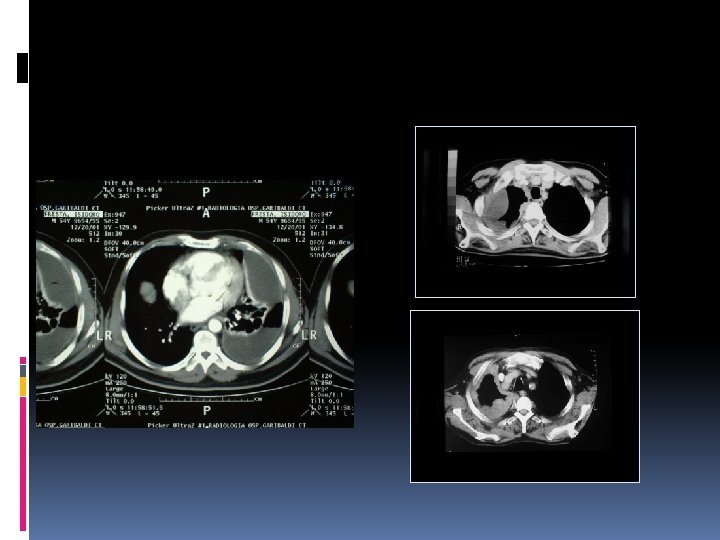

EMPIEMA PLEURICO Diagnosi Esame TAC torace: mette in evidenza la presenza delle sacche di versamento è l’ispessimento della pleura viscerale Esame culturale del liquido pleurico: Spesso la diagnosi è intraoperatoria